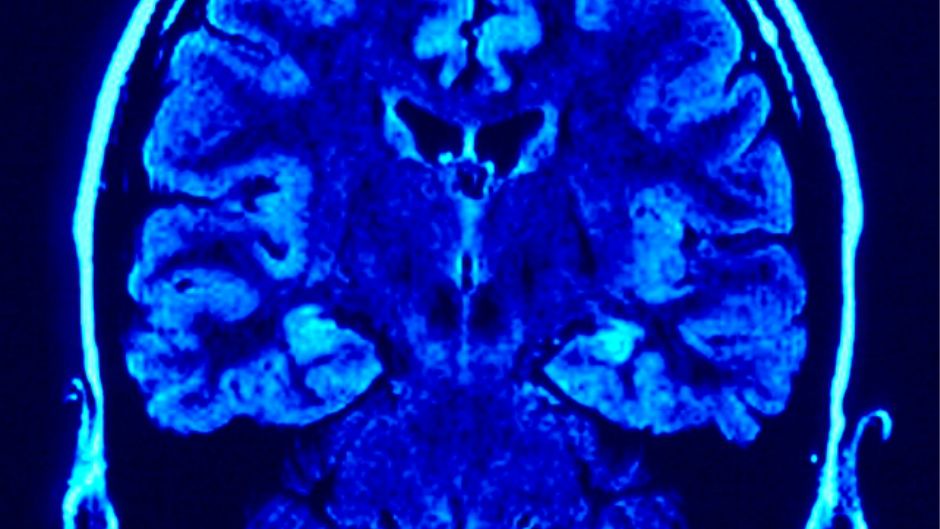

mozak morgue

morgueFile | morgueFile